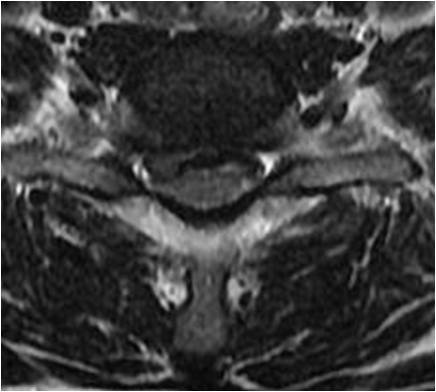

第一天,我跟随张教授上手术。其中一位患者是颈椎后纵韧带骨化症,压迫颈髓局限,张教授进行颈后路2节段椎板切除术。还有一位是脊髓型颈椎病,未充分减压,仅行单节段固定融合术。次日查房,这两位患者的症状得到迅速的缓解,表现出较好的满意度。通过这2例病例,张教授认为:颈后纵韧带骨化症患者,其产生脊髓压迫的主要责任部位在C4、C5,只需针对行减压手术即可;脊髓型颈椎病患者,其产生的病理因素主要是存在颈椎不稳,只要稳定脊柱,就可控制症状。强调对产生症状的病理因素进行有效减压这种理念贯穿于张教授治疗疾患的始终。

颈椎病产生的病理因素是椎间盘,无论是神经根型、还是脊髓型颈椎病。因椎间盘退变可导致脊髓、神经根等受压,亦可形成后方骨赘。那么处理该问题时,就不应该切除椎体,而应该以针对性椎间隙减压即可。所以,张教授在行颈前路手术时,均以单间隙减压充分为目的。无一例行椎体次全切手术。他强调:如有可能,尽量进行单节段固定、融合,强调零切迹的Zero-P的使用。这样,稳定程度高。